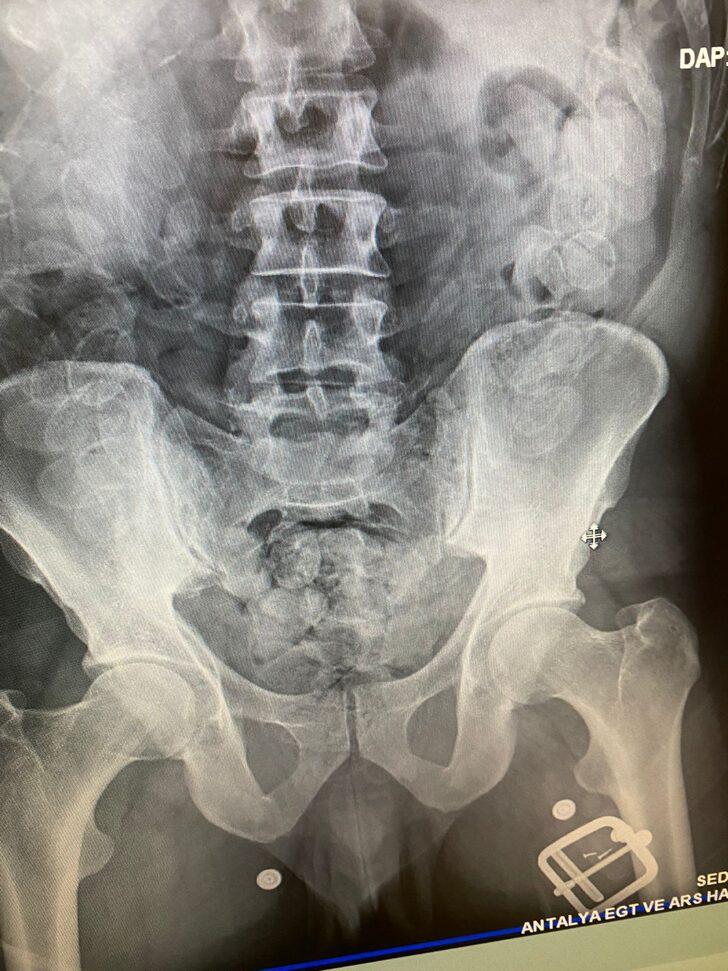

Hudut Kapıları Büro Amirliği ekipleri, Antalya Havalimanı'na gelen Fas uyruklu H.L'nin şüpheli tavırlar sergilemesi üzerine iç muayene gerçekleştirmek üzere hastaneye sevk etti.

Hastanede çekilen röntgenlerde şüphelinin midesinde 100 kapsül daralı 1100 gram macun esrar tespit edildi.